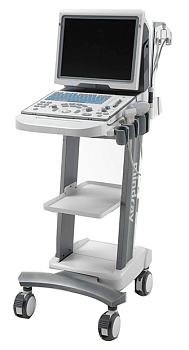

SIUI Apogee 1100 аппарат УЗИ

Описание

Аппарат УЗИ SIUI Apogee 1100 – отличается эргономичным дизайном и наличием передовых технологий визуализации: MFI VS-Flow Nanoview XBeam и др. При создании аппарата ориентировались на максимальную оптимизацию проведения диагностических исследований, чтобы позволить врачу в полной мере насладиться своей работой. Мобильность устройства достигнута небольшим весом для удобной и быстрой транспортировки по отделениям больницы.